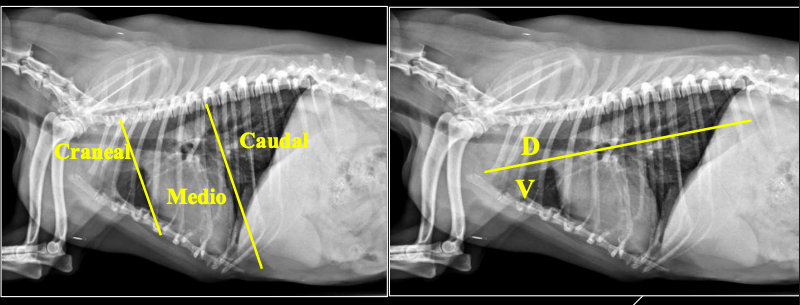

PARTES DEL MEDIASTINO

- Craneal (Cr): Nervios, nodulos linfaticos, vasos (Arteria subclavia izquierda, tronco braquicefalico, vena cava craneal, vena acigos...)

- Medio (Md)

- Caudal (Cd)

Proyecciones: laterolateral derecha y dorsoventral.

Proyección LL:

- Craneodorsal: aorta y atrio derecho.

- Craneoventral: ventrículo derecho.

- Caudodorsal: atrio izquierdo.

- Caudoventral: ventrículo izquierdo.